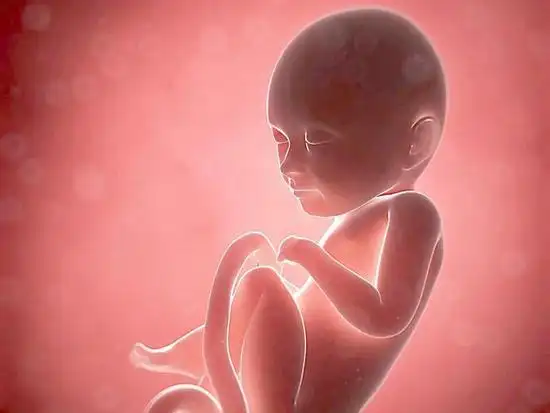

怀孕第18周:胎儿身体的变化

18周胎儿在母体内的真实图片长什么样